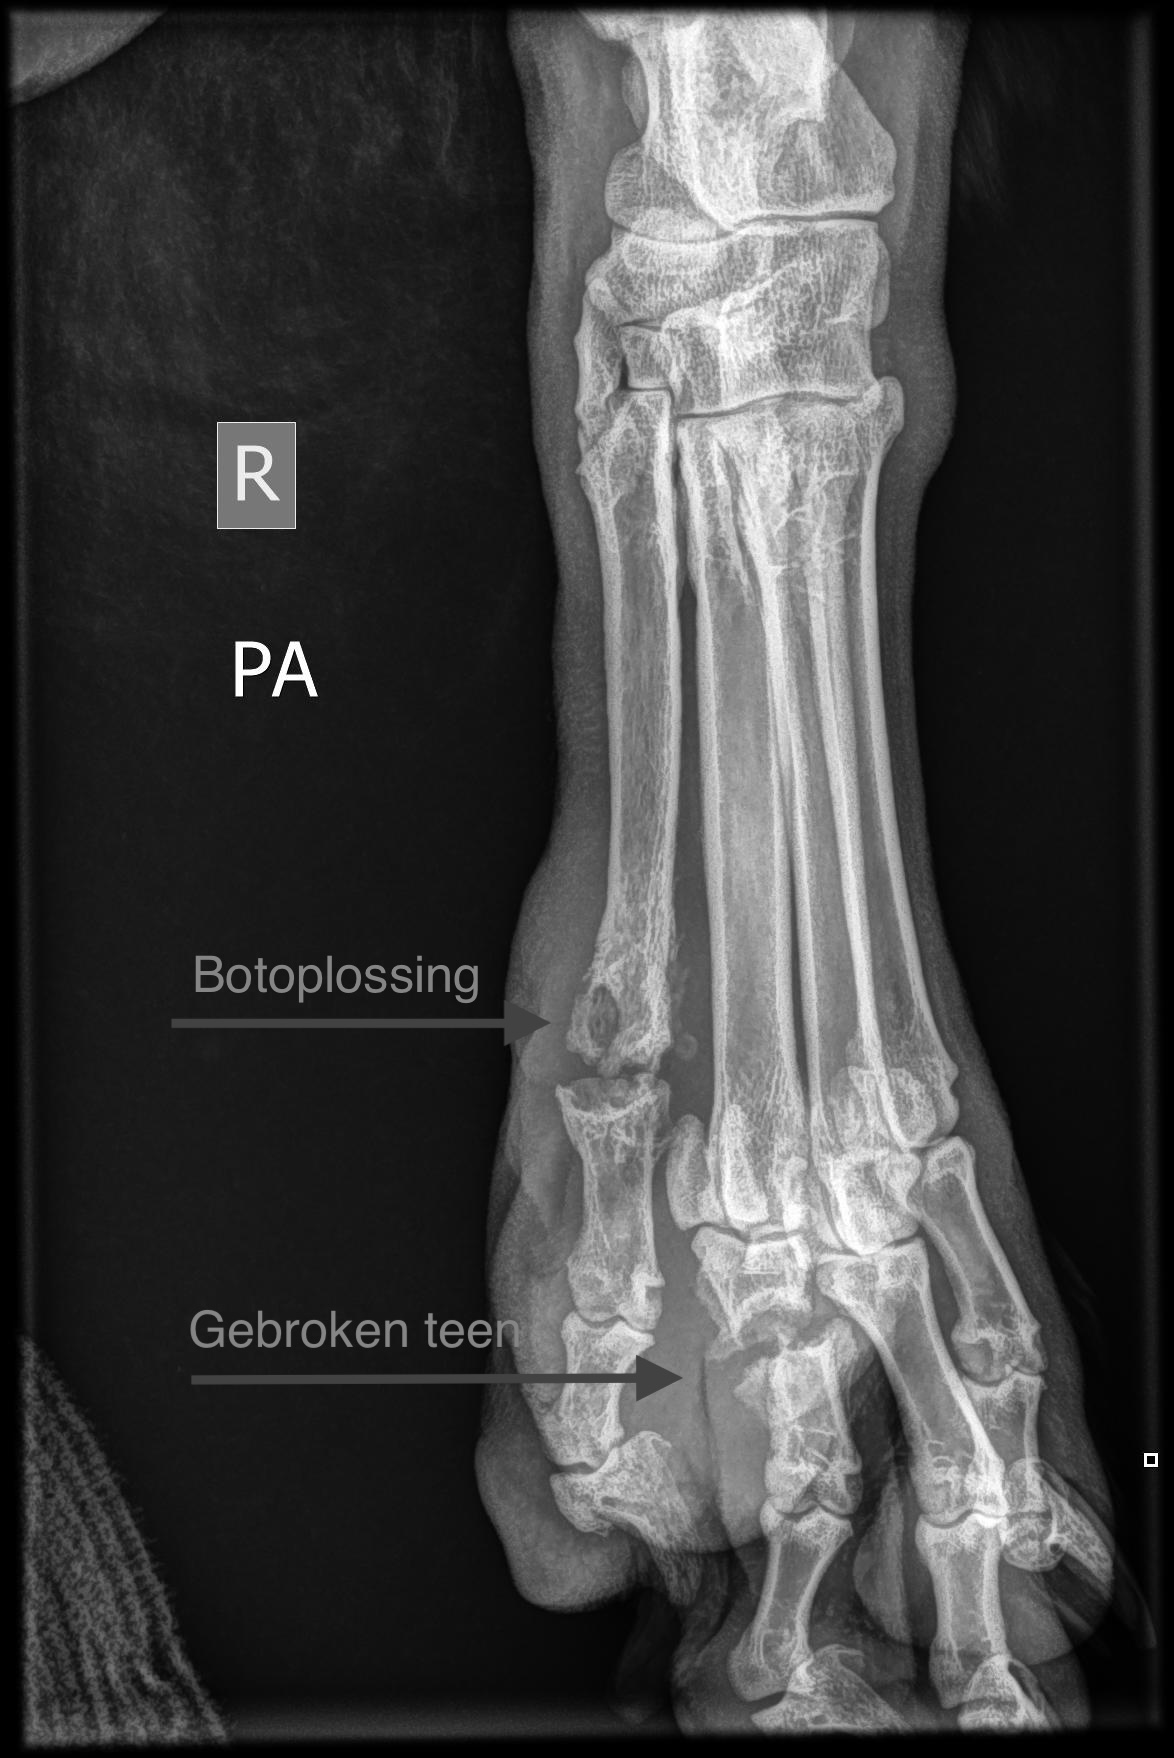

In juli 2025 zagen we Muk en zijn teen voor het eerst. We waren wel onder de indruk van Muk: een grote Leonberger, die je met zachte ogen aankeek. Krijg dat maar eens in beweging, als je hart al niet wegsmelt. Maar 85 kg kan ook heel meewerkend zijn, dat bewees onze Muk. We hebben eerst een kweek afgenomen om te zien met welke bacterie we een wedstrijd aan moesten gaan. En daarna gestart met het zoeken naar de oorzaak van een infectie onder de huid. Vaak is dit bij honden een vreemd voorwerp dat onder de huid is gekropen, waarbij grasaren 🌾 daar berucht om zijn. Maar als snel bleek dat de bacterie rondom de hele teen fistelgangetjes had gemaakt met zelfs botoplossing van een teenkootje. Dit komt zelden voor bij dieren, maar als het optreedt is het moeilijk om daarvanaf te komen. Omdat met locale behandeling niet tot een goed resultaat leidt en de binnenste teen geen dragende teen is, is besloten om de teen met alle fistelgangetjes te verwijderen.

Maar tot onze schrik zagen we op de röntgenfoto ook dat een teenkootje van de andere teen gebroken was. Als hij een teen mist, zal deze gebroken teen harder moeten werken. We hadden nu twee problemen: een fistelende teen met bacteriën (te zien aan het contrastmiddelverloop) en een gebroken teenkootje. We gingen aan de slag: de teen werd verwijderd en een spalk voor de ondervoet werd aangemeten. Het gebroken kootje kon daardoor rust krijgen en gaan helen, terwijl we de operatiewond konden verbinden.